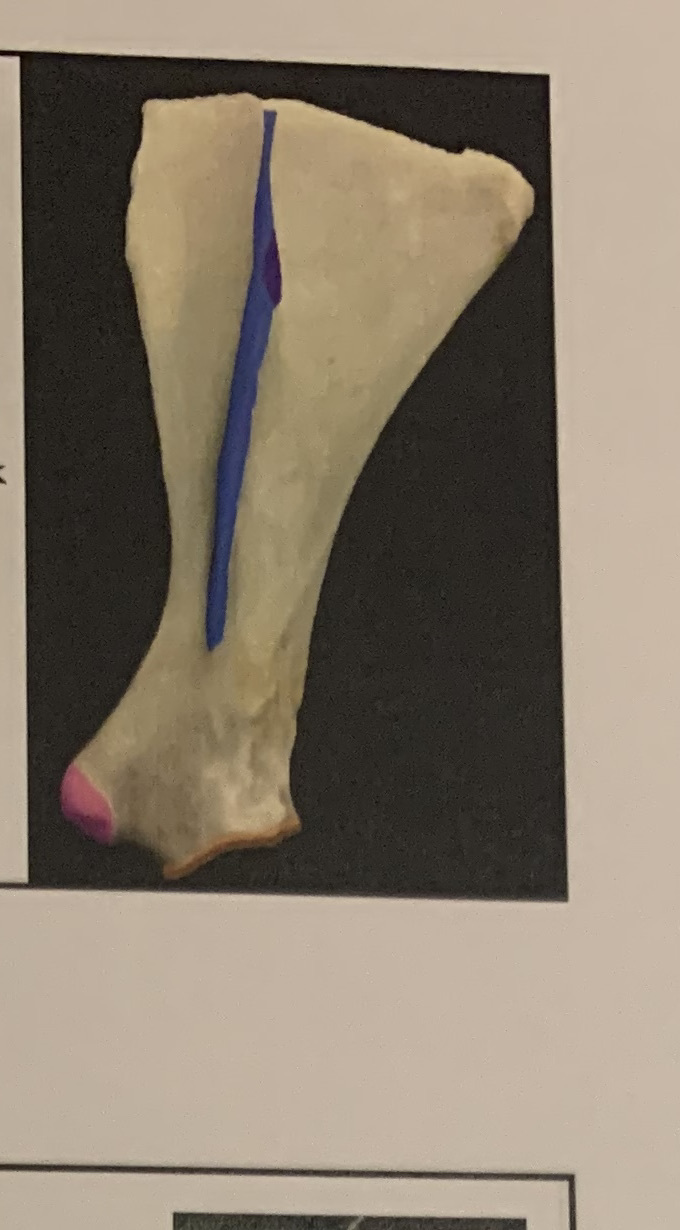

green - deltoid tuberosity

blue - teres major tuberosity

orange - lateral epicondyle

green - origin of the gastrocnemius

yellow - origin of the SDF

blue - peroneus tertius tendon

purple - cranial tibial tendon